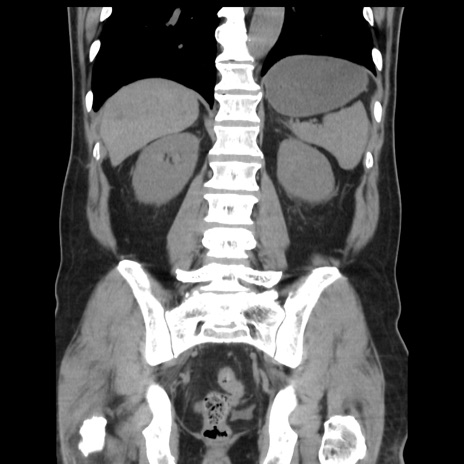

症例16(冠状断像)

【症例】 70歳代男性

【主訴】 腹痛、嘔吐

【現病歴】 約1ヶ月前より間欠的に腹痛と嘔吐あり、当院消化器内科を受診したところCTで多発する肝臓のLDAを指摘され、精査中であった。以降は消化器症状は安定していたが、2日前より嘔気と腹痛があり、同日より排便・排ガスが消失した。改善認めず、 本日、救急外来を受診した。

【既往歴】 大腸ポリープ切除後。

【身体所見】意識清明・会話良好、BT 36.3℃、BP 127/80mmHg、 P 80bpm、腹部:膨満あり、平坦・軟、上腹部正中および下腹部正中に圧痛あり、反跳痛なし、筋性防御なし。

【データ】WBC 7200、CRP 0.77